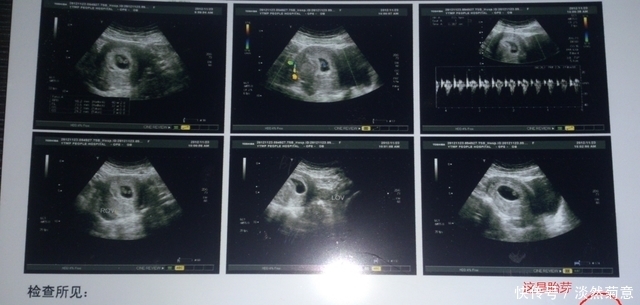

下面这份「孕期产检一览表」,总结了从 第一次正式产检(孕12周)到宝宝出生前 最后一次产检(孕40周),每次产检的检查时间、是否空腹、检查的目的、检查项目及注意事项等,很全面,孕妈们可以收藏,每次产检前找出来看看。

从这个产检表中可以看到孕期280天,总共有13次产检,第一次正规产检是怀孕12周。